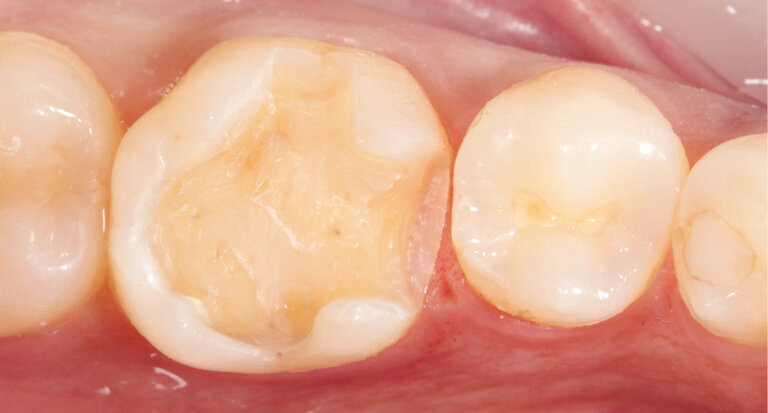

The attachment point was easy to smooth out with fine-grit diamonds. This was followed by extraoral polishing using composite polishers (e. g. OptraPol®) (Fig. 5). Particularly noteworthy was the speed with which the restoration was polished to a high gloss. It only took a few seconds to achieve a glossy surface (Fig. 6). Composites do not require an additional glaze firing cycle. This has a positive effect on the time resources of the practice.